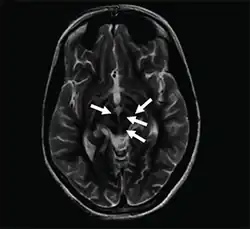

| Axial T2-weighted MRI of the brain at the level of the midbrain showing the characteristic ‘face of the giant panda’ sign, with normal red nuclei and substantia nigra (pars reticulata) against a background of hyperintensity in the tegmentum, as well as hypointensity of the superior colliculi | |

The face of the giant panda sign, panda sign of the midbrain or double-panda sign is a characteristic "panda's face" appearance in magnetic resonance imaging (MRI) images of people with Wilson's disease. Along with Kayser–Fleischer rings, the sign is helpful in diagnosis.[1]